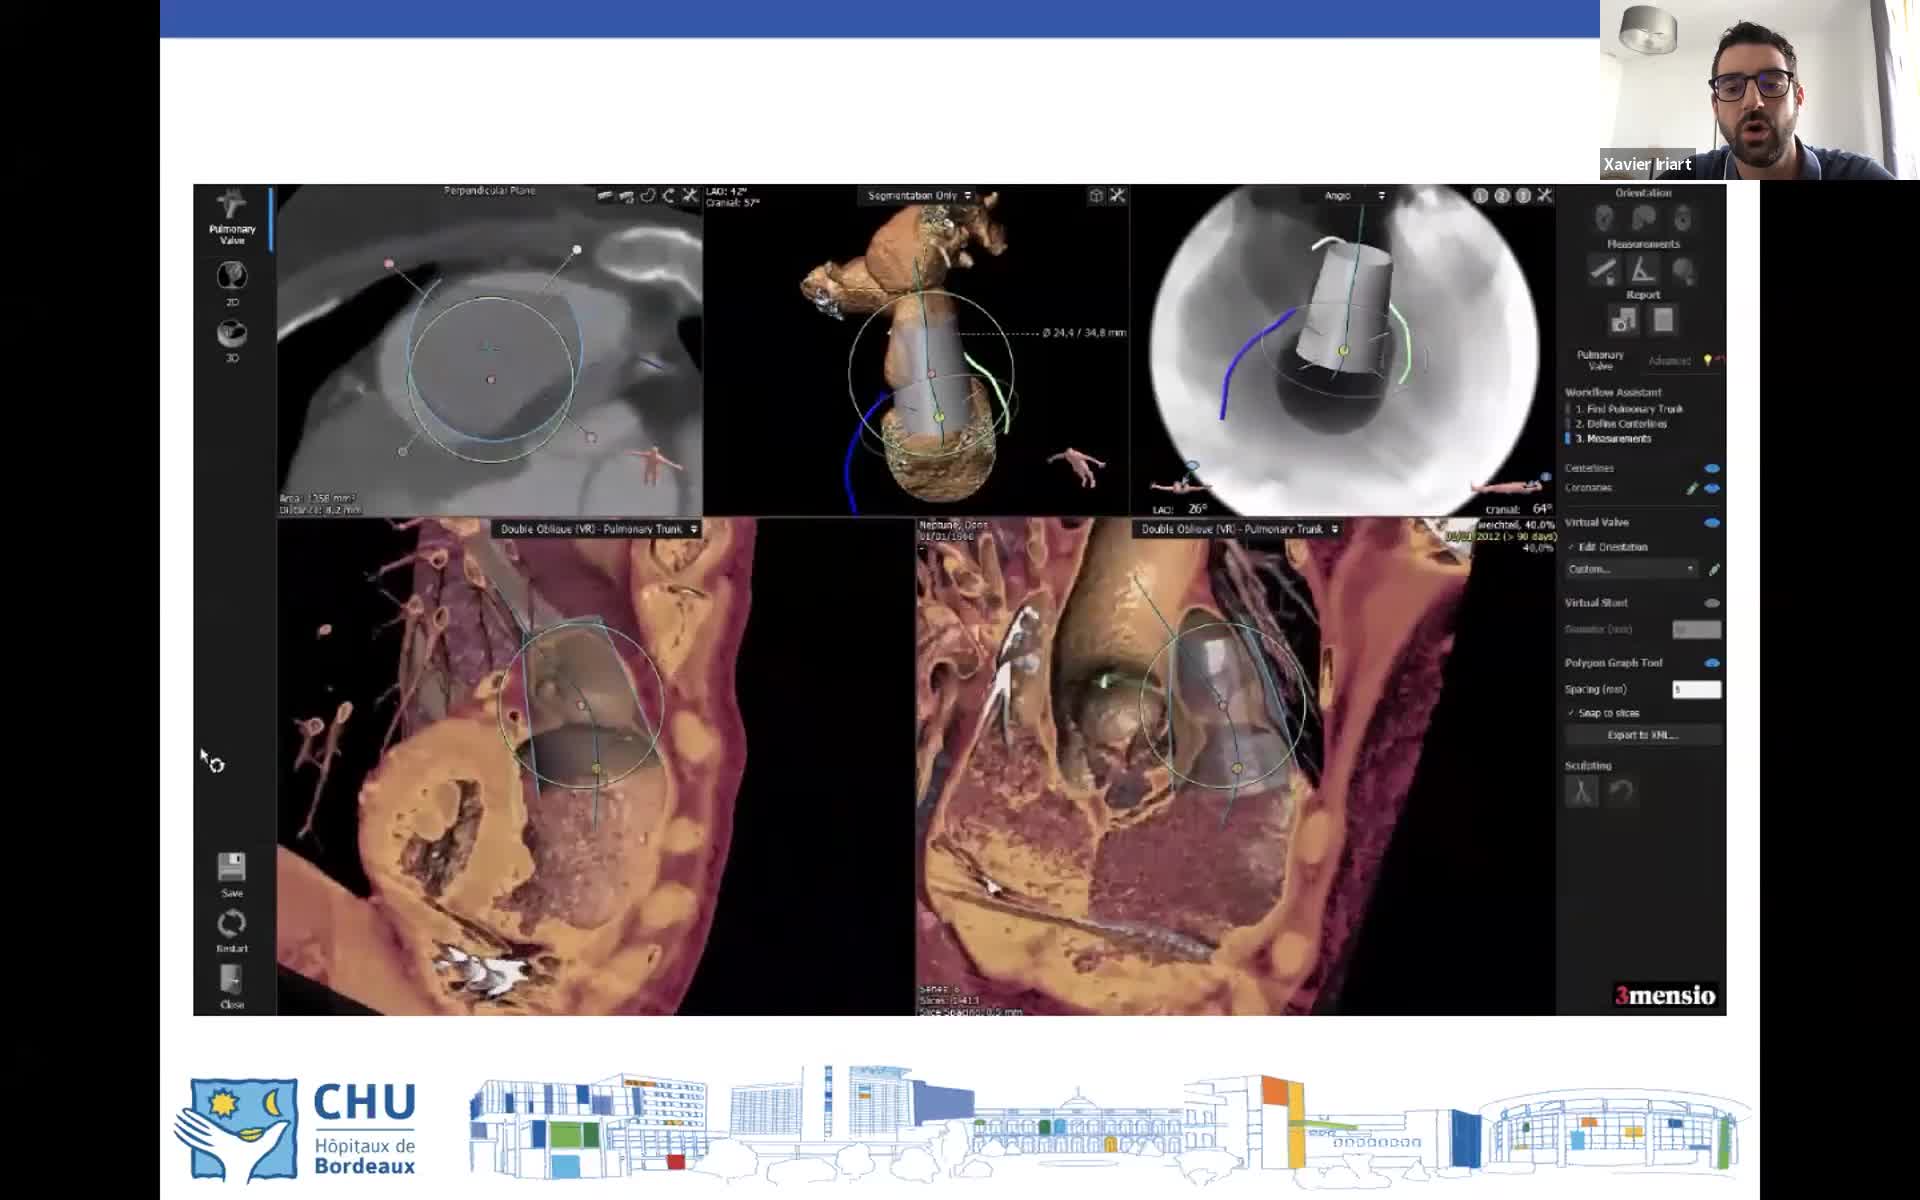

Cathlab Live Cases